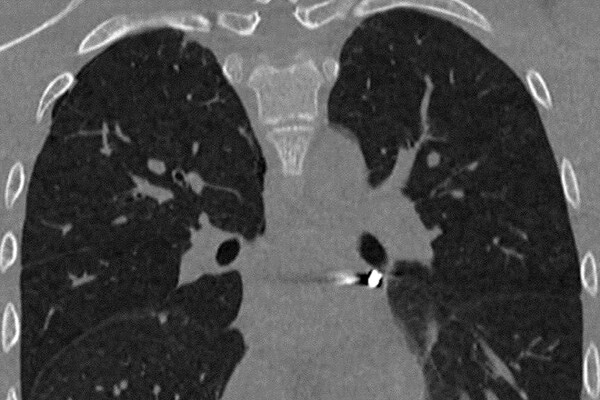

«Инородное тело мигрировало в опаснейшую зону — между легочными венами у задней поверхности предсердия. Мы выполнили малоинвазивную операцию со вскрытием перикарда, работая буквально в миллиметрах от жизненно важных структур», — рассказал заведующий отделением детской хирургии № 2 Никита Степаненко.